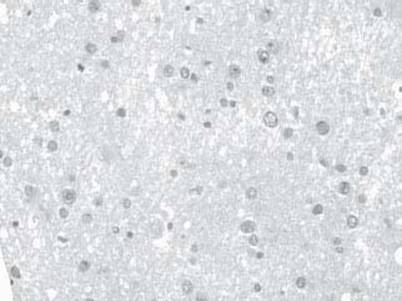

7. A 42-year-old woman presented with low-grade fevers of 1-month duration, headache, photophobia and neck stiffness for at least 1 week, and altered mental status on admission. A lumbar puncture was performed, and the opening pressure was 30 cm H2O. CSF analysis showed 0 RBCs, 55 WBCs with 70% lymphocytes (normal up to 5 lymphocytes/μL), protein of 60 mg/dL (normal up to 45 mg/dL), and glucose of 50 mg/dL. India ink smear was positive in the CSF. The patient eventually died, and the brain specimen is shown in Figure 15.1. Which of the following is the most likely etiologic agent?

FIGURE 15.1 Brain specimen. Courtesy of Dr. Richard A. Prayson. Shown also in color plates

On the basis of the clinical history, presentation, elevated CSF opening pressure, and the presence of a positive India ink smear, this patient has cryptococcal meningitis, which is caused by the encapsulated yeast Cryptococcus neoformans. Furthermore, the histopathologic specimen demonstrates budding yeasts near blood vessels and surrounded by an inflammatory infiltrate, which is consistent with infection by this organism.

Cryptococcal meningitis usually occurs in immunocompromised patients and is an opportunistic infection seen in advanced HIV infection, usually when CD4 counts fall below 200 cells/μL. However, it may rarely be seen in otherwise immunocompetent patients; in such cases, a history of exposure to bird droppings, as occurs with roofers, may be elicited.

Patients usually present with fever, headache, neck stiffness, personality and behavioral changes, and altered mental status. Brain CT scan and MRI are performed to rule out other conditions and may demonstrate hydrocephalus, gelatinous pseudocysts, infarcts, or cryptococcomas. Lumbar puncture demonstrates an increased opening pressure, and CSF analysis shows mononuclear lymphocytosis with increased protein and low glucose levels. India ink smear is not very sensitive; however, it is useful when it is positive. Cryptococcal antigen detection in the CSF is rapid, sensitive and specific, and clinically useful, since fungal culture may take several days to weeks for a positive result to be obtained.